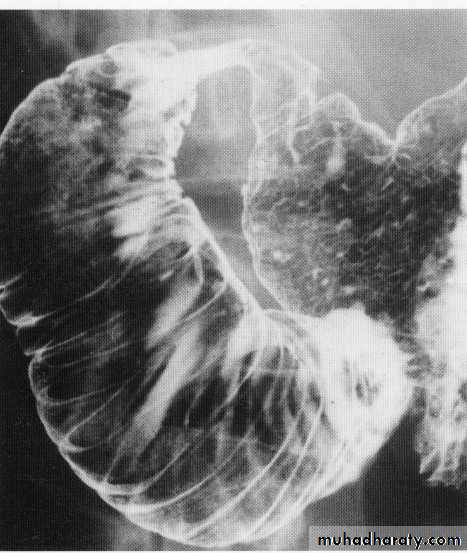

Gastric lymphoma